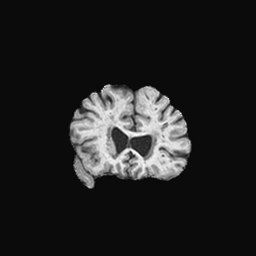

Exp. 2: Fetal brain data is used to test the robustness of our approach under real conditions. Fetuses younger than 30 weeks very often move a lot during examination. Fast MRI sequences allow artifact free acquisition of individual slices but motion between slices corrupts consistent 3D information. Fig. 3 shows that our method is able to accurately predict also under these conditions. For this experiment we use from three orthogonally overlapping stacks of ssFSE slices covering the fetal brain with approximately 20-30 slices each. We are ignoring the stack transformations relative to the scanner and treat each individually. For , 28 clinically approved motion compensated brain reconstructions are resampled into a volume with spacing. A density of 500 unique sampling normals has been chosen via the Fibonacci sphere sampling method with 25 sampling planes evenly spaced between -25 to +25 on the Z-axis. This gives a plane spacing of 2mm, sampling only the middle portion of the fetal brain. Training took approximately 10hrs for 30 epochs. Prediction, i.e., the forward pass through the network, takes approx. 12 ms/slice.

0..5.2 Exp. 2:

Slices, from a motion corrupted MRI stack, are segmented and cropped. Since there is no ground truth for the queried images, an arbitrary fetal atlas is used for visualization in Fig. 11 and 12.